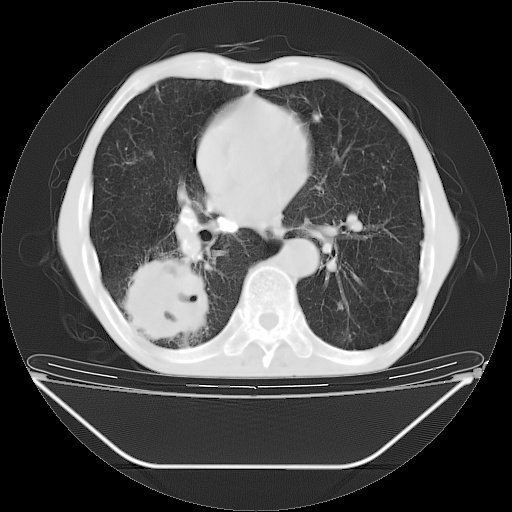

以下是引用随光逐影在2008-8-25 22:03:00的发言:[br]1)考虑右肺下叶周围性肺癌并肺内转移,腰椎附件转移。2)左上肺结核(结核球形成)。3)双肺肺气肿(多发肺大泡形成)。4)双肺门区及纵隔内多发淋巴结钙化。

以下是引用zsl6918在2008-8-25 21:55:00的发言:[br]符合右肺周围性肺癌并肺内转移,左肺结核球。双肺肺气肿。腰椎附件转移。

以下是引用qc80012345在2008-8-26 6:14:00的发言:[br]符合右肺周围性肺癌并肺内转移,左肺结核球。双肺肺气肿。腰椎附件转移。